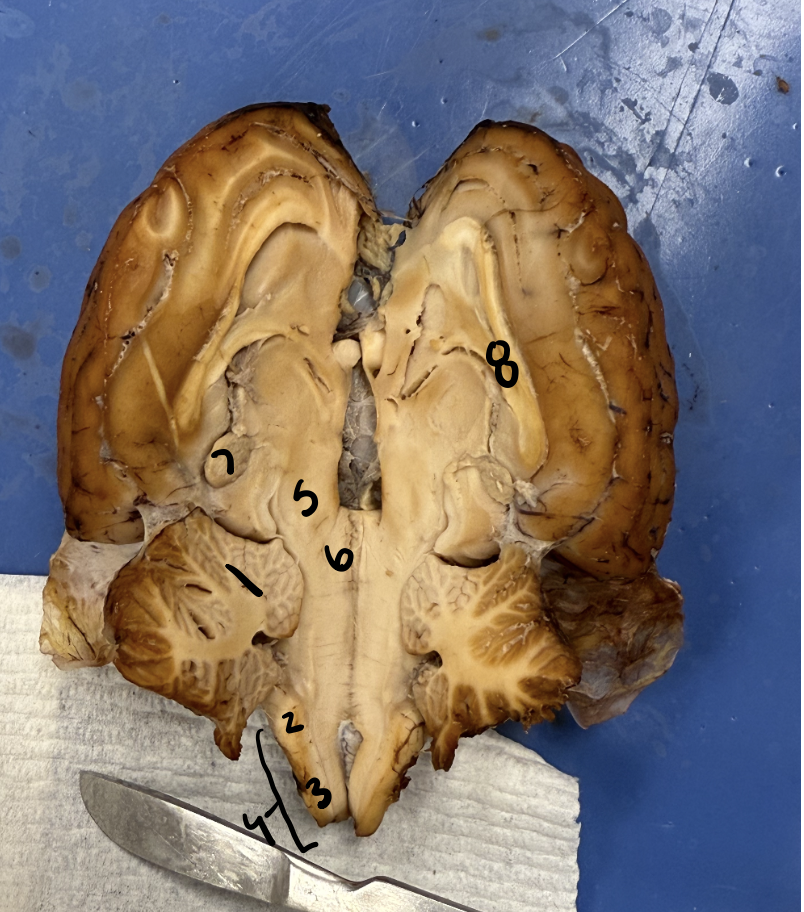

cerabellum

2

pons

3

medulla

4

spinal cord

5

thalmus

6

hypothalmus

7

peneal gland

8

Corpus calusom